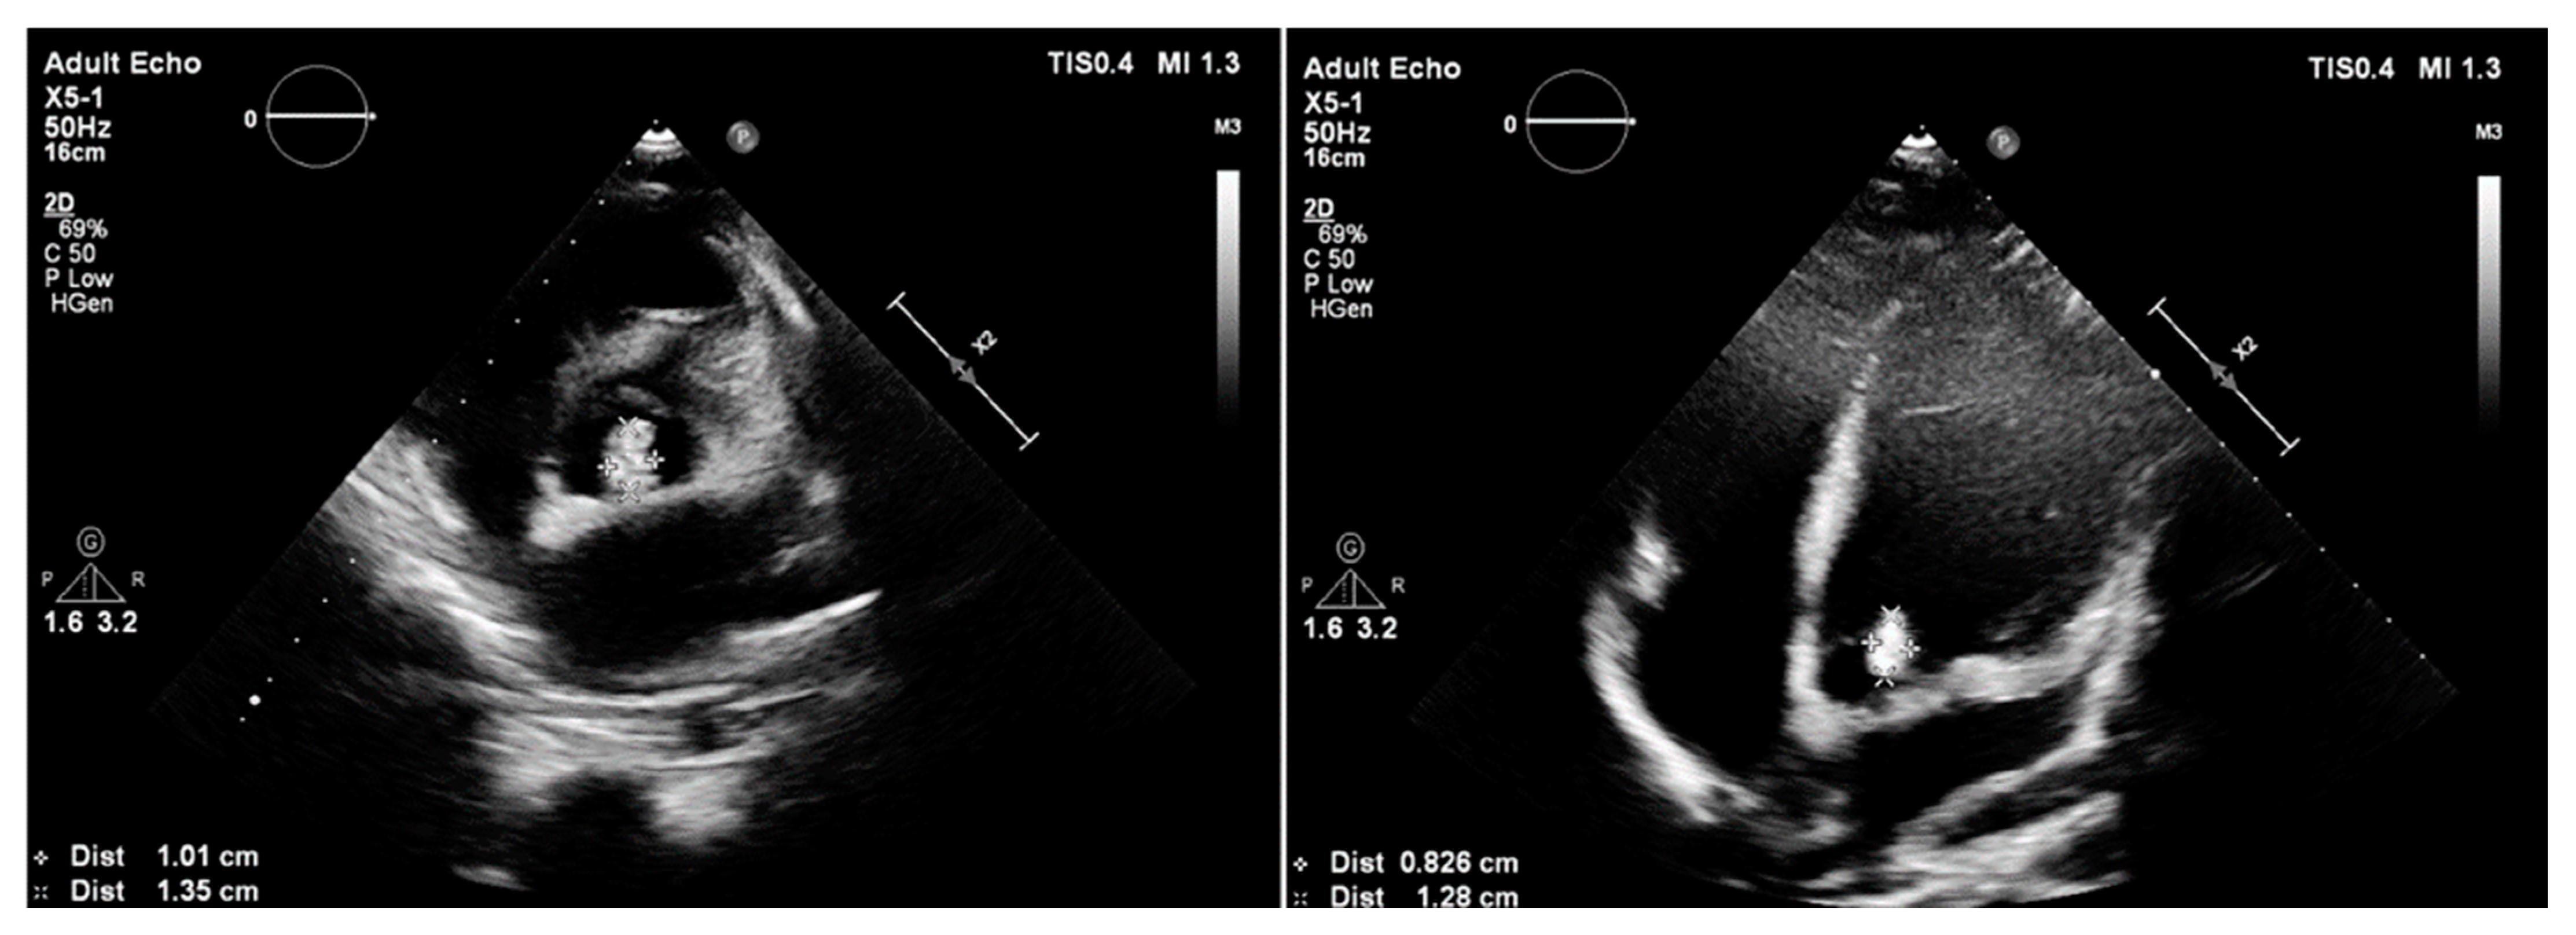

A nearly-16-year-old girl was admitted to the Pediatric Department because of recurrent fever and hepatosplenomegaly. In the past, the girl had undergone procedures such as complete Fallot Tetralogy repair during infancy, Contegra replacement by CorMatrix conduit in pulmonary position during her preschool years, numerous catheter interventions with percutaneous stenting of LPA, and Resilia 23 Edwards implantation two years before her current hospitalization in the Pediatric Department. The patient had suffered from frequent respiratory system infections, recurrent fever, anemia, and microhematuria with cast erythrocytes in urine for the last six months. The teenager did not present other symptoms; however, the clinical examination revealed a systolic heart murmur of 3/6 in LS over the PV, and a significantly enlarged liver and spleen. CRP (20.40 mg/L) and erythrocyte sedimentation rate (45 mm/1 h, 78 mm/2 h) (ESR) were slightly elevated but hemoglobin (7.2 g/dL) (HGB) and erythrocyte mean corpuscular volume (71.0) (MCV) levels were significantly decreased. The treatment started with ceftriaxone (2 g twice/day), then cefixime (400 mg/day) was administered and two units of packed red blood cells were transfused. The patient was transferred to two upper reference departments because of insufficient CRP and the decrease in other inflammation indicators levels and persistent HGB level, where initially the formerly-administered antibiotic therapy was continued. The patient’s general clinical state was stable; the ankles were slightly swollen. Microhematuria with casts erythrocytes, proteinuria (76.9 mg/dL), and elevated levels of protein in 24-h urine (172.50 mg/dL) collection were seen; eGFR was mildly reduced (60 mL/min/1.73 m2). Creatinine (1.57 mg/dL), urea (39.0 mg/dL), rheumatic factor (216 Iu/mL) (RF), CRP (20.00 mg/L), lactate dehydrogenase (313 U/L) (LDH), and d-dimer (1893 μg/L) levels were elevated. The antinuclear antibodies (+) (ANA) screening was slightly positive but anti-neutrophil cytoplasmic proteinase 3 antibodies (PR3-ANCA) were highly positive (+++). All the results of the blood culture samples taken according to the ESC procedure were negative. The former antibiotic therapy was replaced with cloxacillin (firstly 2 g, 6 times/day, next 3 g, 4 times/day), ampicillin (firstly 2 g, 6 times/day, next 3 g 4 times/day), and ceftazidime (2 g, 3 times/day). The teenager’s liver and spleen were still enlarged, the kidneys and pelvicalyceal system were in ultrasonographical normal condition, and an insignificant ovarian cyst was visible on abdominal ultrasonography. The TTE examination showed the hypertrophied and dilated RV, reduced RV ejection fraction (EF), enlarged right atrium (RA), reduced IVC respiratory variability, abnormal interventricular septal motion, II degree tricuspid regurgitation with PG 100 mmHg, II degree PV regurgitation with max 36 mmHg, and right ventricle outflow tract (RVOT) stenosis with maximum PG 60 mmHg. The 2.5 mm and 3 mm slightly-built ballotable vegetations were weakly visible on Resilia in TTE (Figure 4A,B), but in TOE all vegetations were well-visible.

Figure 4.

Transthoracic echocardiography; (A) the arrow point at ballotable vegetations; (B) II degree PV regurgitation; PV—pulmonary valve.